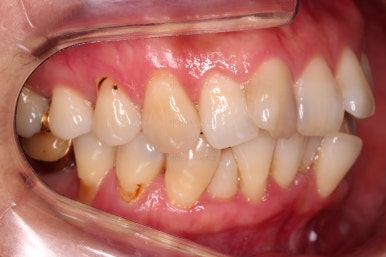

임플란트가 이미 있을 경우

임플란트는 교정이 되지 않습니다.

뼈에 단단히 붙어 있기 때문에 힘을 줘도 원하는 위치로 이동되지 않습니다.

이번 환자분의 경우 임플란트가 어금니 크기보다 작게 제작이 되어 있어서 추후에 교합을 맞추기도 곤란한 상황이었어요.

그래서 교정 후에 임플란트 뿌리 부분은 그대로 사용하고 머리 부분만 재제작 하기로 했습니다.